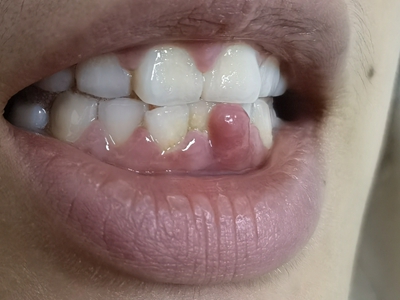

牙龈瘤是指发生在龈乳头部位的炎症反应性瘤样增生物,好发于女性,前磨牙区最为常见。牙龈瘤来源于牙周膜及牙龈的结缔组织,因其无肿瘤的生物学特征和结构,故非真性肿瘤,但切除后易复发,因此切除务必彻底,必要时拔除相关牙齿。

牙龈瘤多发于女性,以青年及中年人为常见,多发生于牙龈乳头部,位于唇、颊侧者较舌、腭侧者多,最常见的部位是前磨牙区。肿块较局限,呈圆形或椭圆形,有时呈分叶状,大小不一,直径由几毫米至数厘米。

肿块有的有蒂,如息肉状;有的无蒂,基底宽广,生长较慢,但在女性妊娠期间可能迅速增大。较大的肿块可以遮盖一部分牙及牙槽突,表面可见牙压痕,易被咬伤而发生溃疡,伴发感染。随着肿块的增长,牙槽骨壁逐渐被破坏,牙可能发生松动、移位。